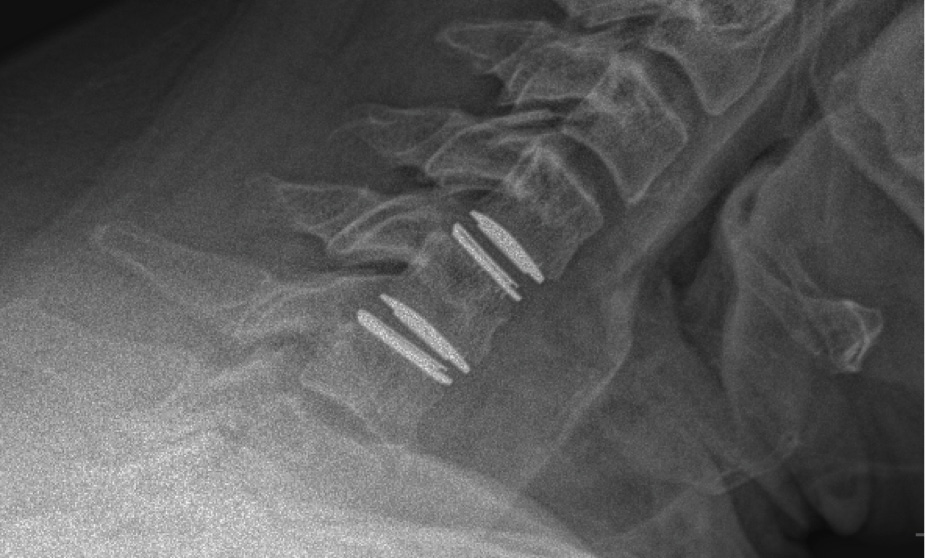

During the procedure, prodisc C Vivo fit well within the C4-5 concave endplate. I expected to use a flat endplate prodisc C SK at C5-6, however I trialed the domed prodisc C Vivo and it actually looked good, so I unexpectedly used matching implants.

It was very helpful to have the flexibility to use either a flat or a domed implant at either level. Having the different size options available to truly match patient anatomy that the Match-the-Disc™ System provides enabled me to avoid having to alter the patient’s anatomy to fit the device.